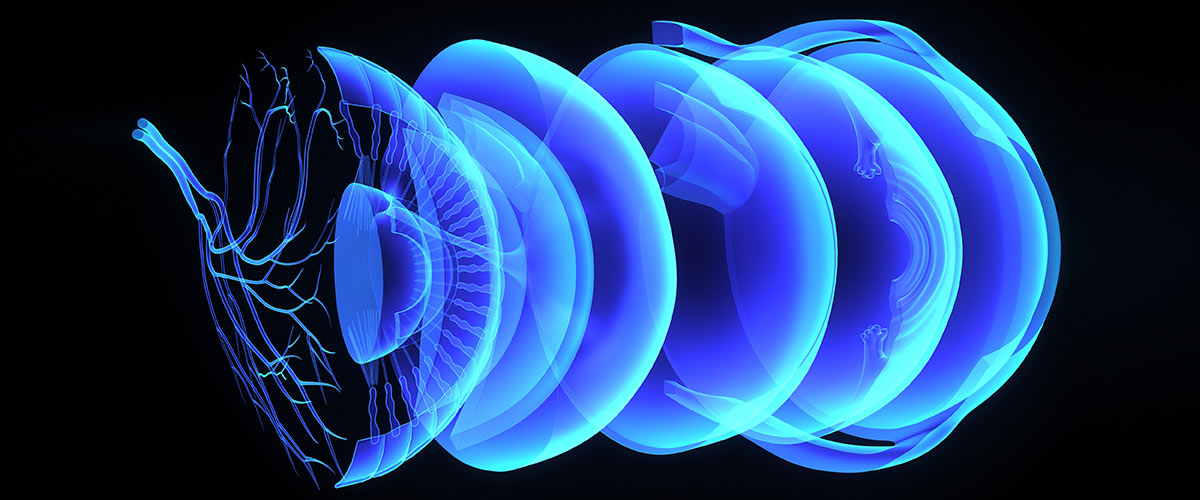

Jaga Mata Anda: Cara Melindungi Penglihatan dari Dampak Cahaya Biru

Di era digital, kita menghabiskan berjam-jam setiap hari di depan layar ponsel, komputer, atau televisi. Namun, cahaya biru yang dipancarkan oleh perangkat ini dapat menyebabkan ketegangan mata, kekeringan, […]